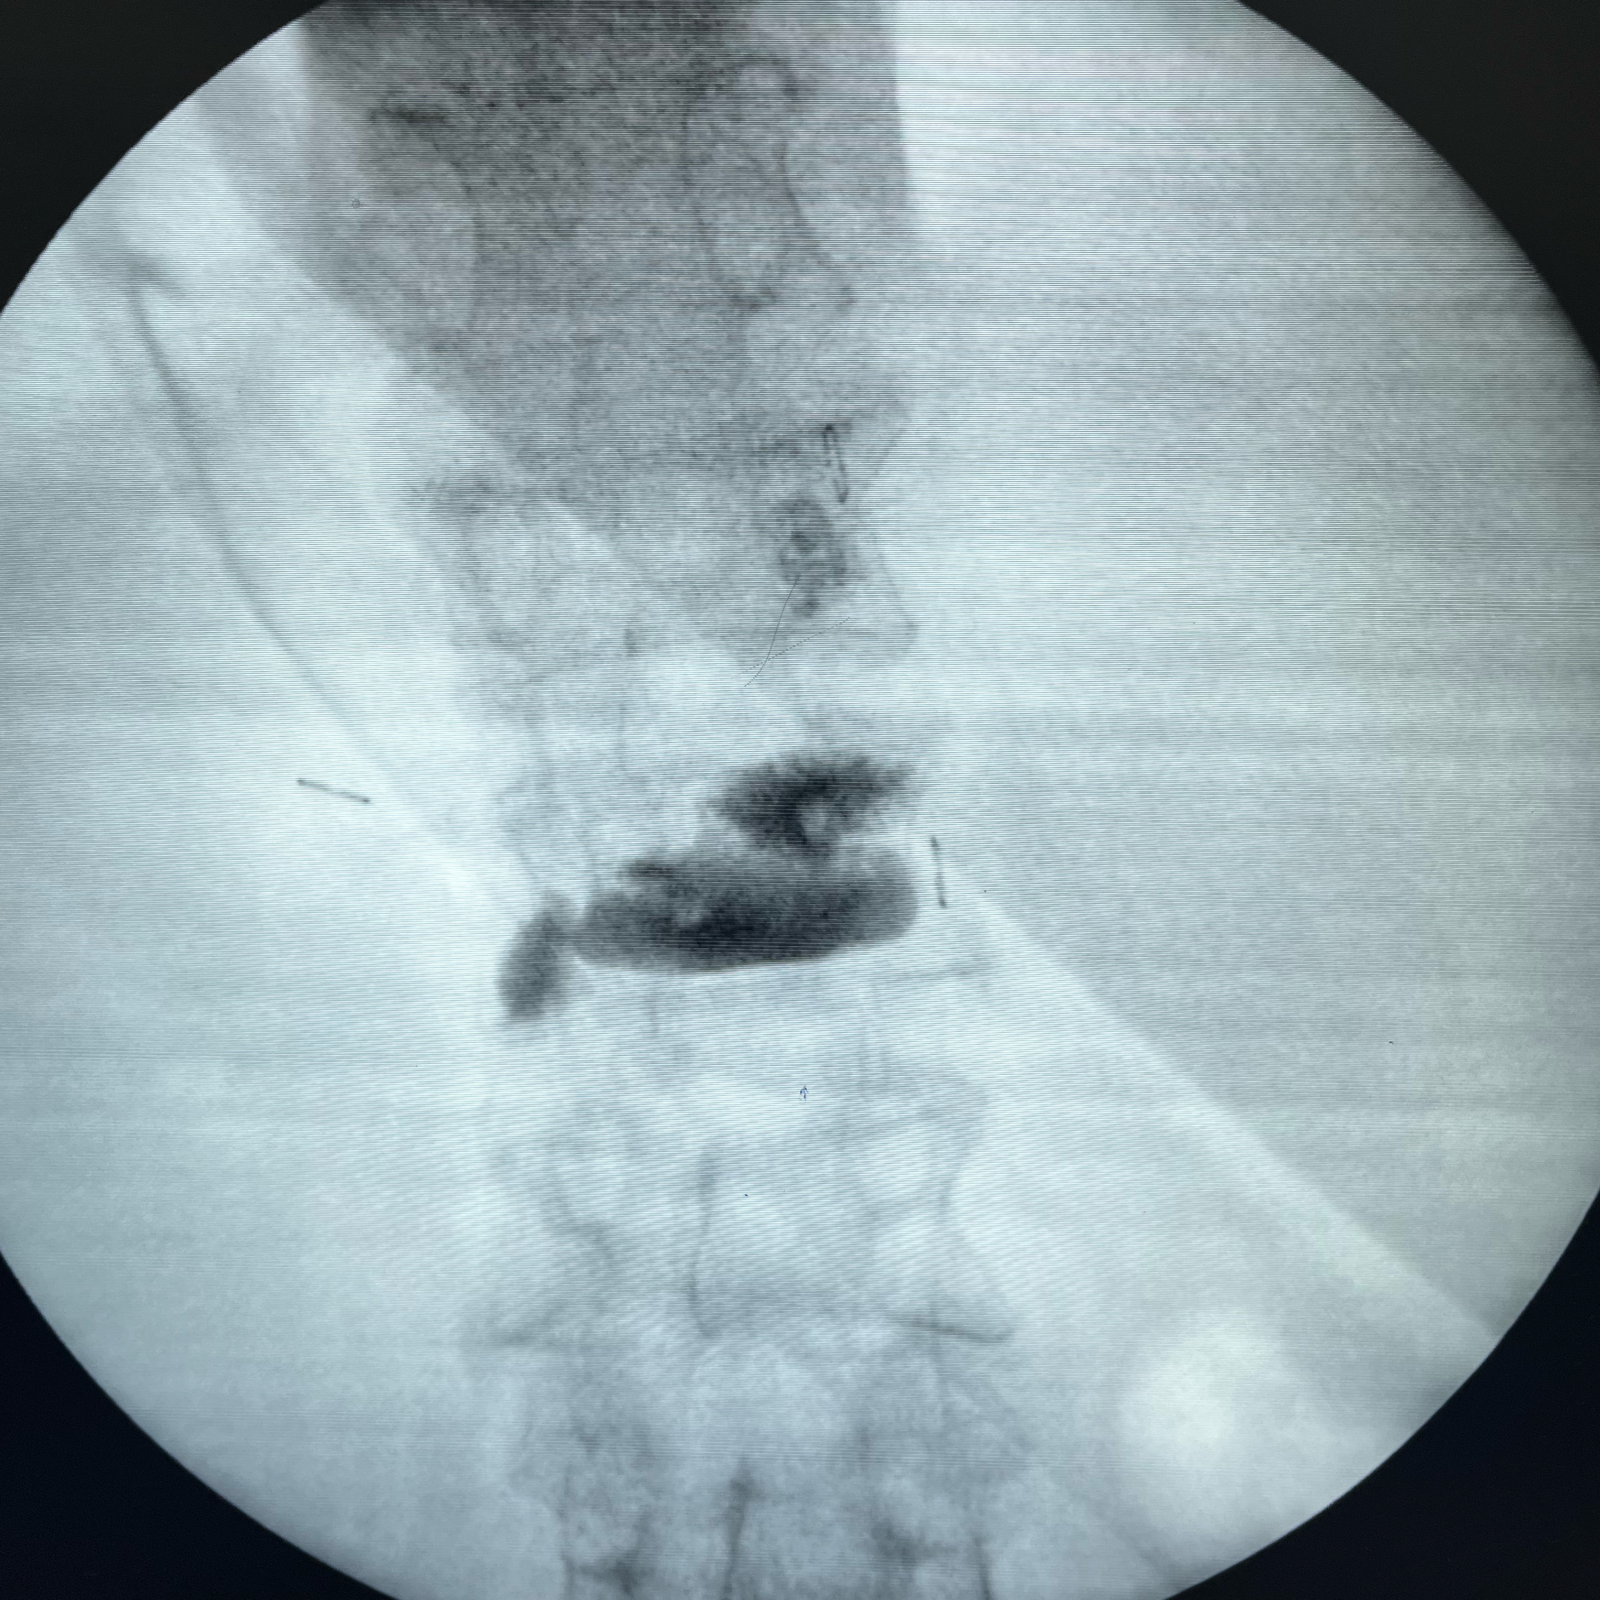

Vertebroplasty for Osteoporotic Spinal fractures